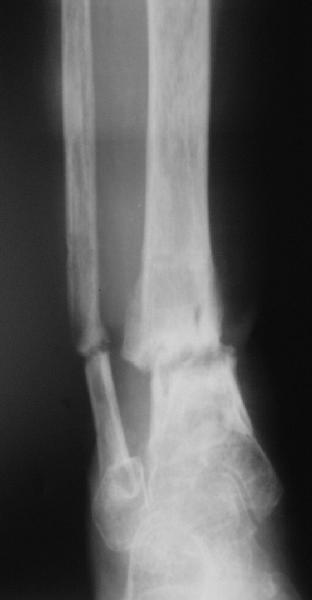

Alexander Chelnokov 18 Апрель 2005, 18:48

e> сустав,стержень можно провести проксимальнее сустава, фиксируя только таран.

А такая травма сустава не приводит к артрозу? Это же не спица.

e> Как ты думаешь, какова перспектива голеностопного сустава с такой исходной

e> мобильностью?

Мне интуиция подсказывает, что замыкать сустав сейчас не стоит.

e> голеностопа разрушен, что при восстановлении оси голени и нагрузке приведет

e> к ОА. Предвидеть в какой степени он будет выражен невозможно, вполне

e> вероятен последующий артродез.

А если панартродез разу - на суставы среднего тарза и колено как он повлияет? Даме 72 года (она, кстати, терапевт в прошлом), функциональные требования не очень высоки, масса тела невелика... Так что - может, и проскочим со всеми суставами?

В общем, начали c аппарата - нложили, малоберцовую внизу пересекли, выбрали люфт, раз дальше сопротивление пошло - выведем постепенно.

Картинки приложены. Жду комментариев.